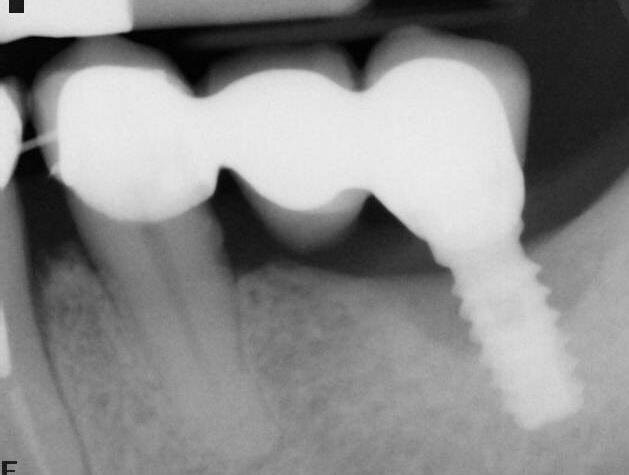

A termine del trattamento descritto in precedenza da un punto di vista clinico abbiamo ottenuto un ripristino dei parametri di salute dell’impianto ovvero la scomparsa del sanguinamento dell’edema e della purulenza, in oltre si è verificata una riepitelizzazione dei tessuti molli limitrofi l’impianto. Da un punto di vista radiografico abbiamo ottenuto la neoformazione di osso attorno alle spire dell’impianto (con relativo aumento della stabilità) che a inizio terapia era da considerarsi potenzialmente come perso. La radiografia a 60 gg prima ed a 1 anno mostrano quanto prima descritto, ovvero un ripopolamento di componenti cellulari ossei sull’impianto con un recupero di 3 spire implantari (Figg. 7-9).